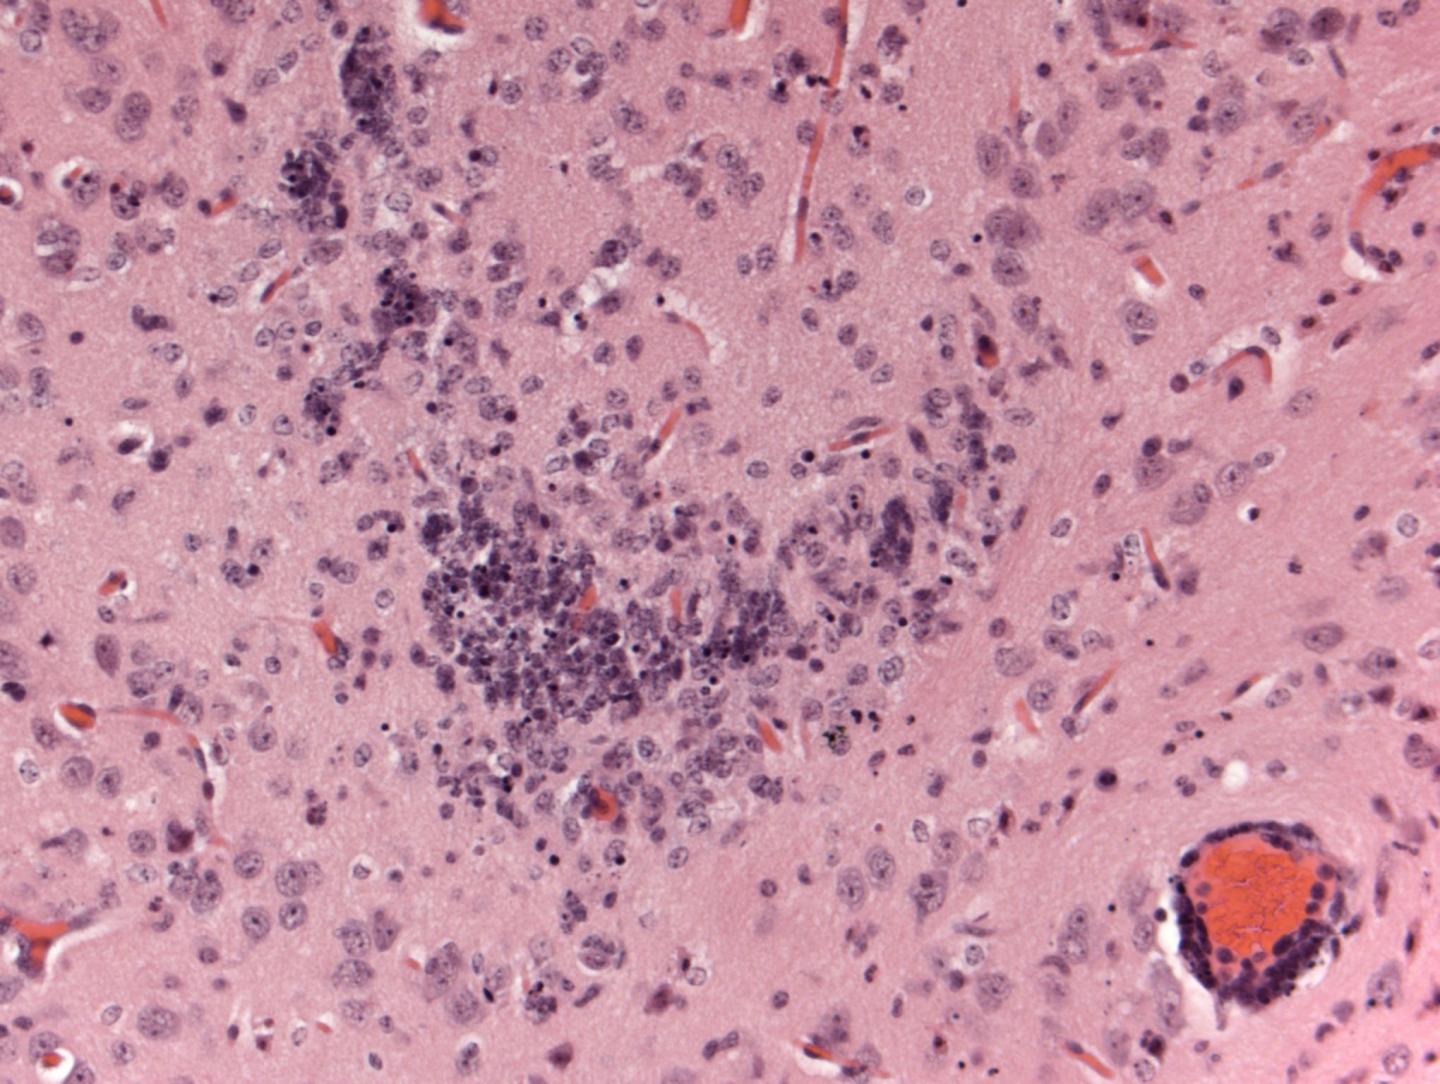

Viral RNA (which indicates virus invasion of the tissue and subsequent virus multiplication) was detectable on day 3 after infection in all tissues tested, including blood, spleen, liver, ovary, and brain. Viral RNA levels ranged from ~107 in blood and liver to nearly 1011 in brain (where they continued to increase until the death of the animals). These levels are within the range of viral RNA loads detected in human blood serum and breast milk (106), semen (107), and urine (108). The researchers also observed abnormalities in the brain and eyes of the infected A129 mice.

In an accompanying Commentary, M. Javad Aman from Integrated BioTherapeutics, Inc. in Gaithersburg, USA, and Fatah Kashanchi, from the George Mason University in Manassas, USA, discuss the recent advances on mouse models for ZIKV disease and state that collectively, the recent papers mark "an important turning point in Zika virus research and enable in vivo testing and evaluation of candidate vaccines and therapeutics". Referring specifically on the study by Dowall and colleagues, they recommend that future research should examine to what extent the abnormalities in the mouse brain reflect the CNS abnormalities in humans.